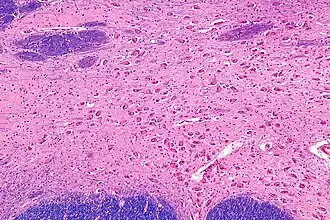

![]() Intermediate magnification micrograph of the nucleus basalis. LFB-HE stain. | |

The nucleus basalis in humans is a somewhat diffuse collection of large cholinergic neurons in the basal forebrain.[2] The main body of the nucleus basalis lies inferior to the anterior commissure and the globus pallidus, and lateral to the anterior hypothalamus in an area known as the substantia innominata.[1] Rostrally, the nucleus basalis is continuous with the cholinergic neurons of the nucleus of the diagonal band of Broca.[1] The nucleus basalis is thought to consist of several subdivisions based on the location of the cells and their projections to other brain regions.[2] Occasional neurons belonging to the nucleus basalis can be found in nearby locations such as the internal laminae of the globus pallidus and the genu of the internal capsule.[1]